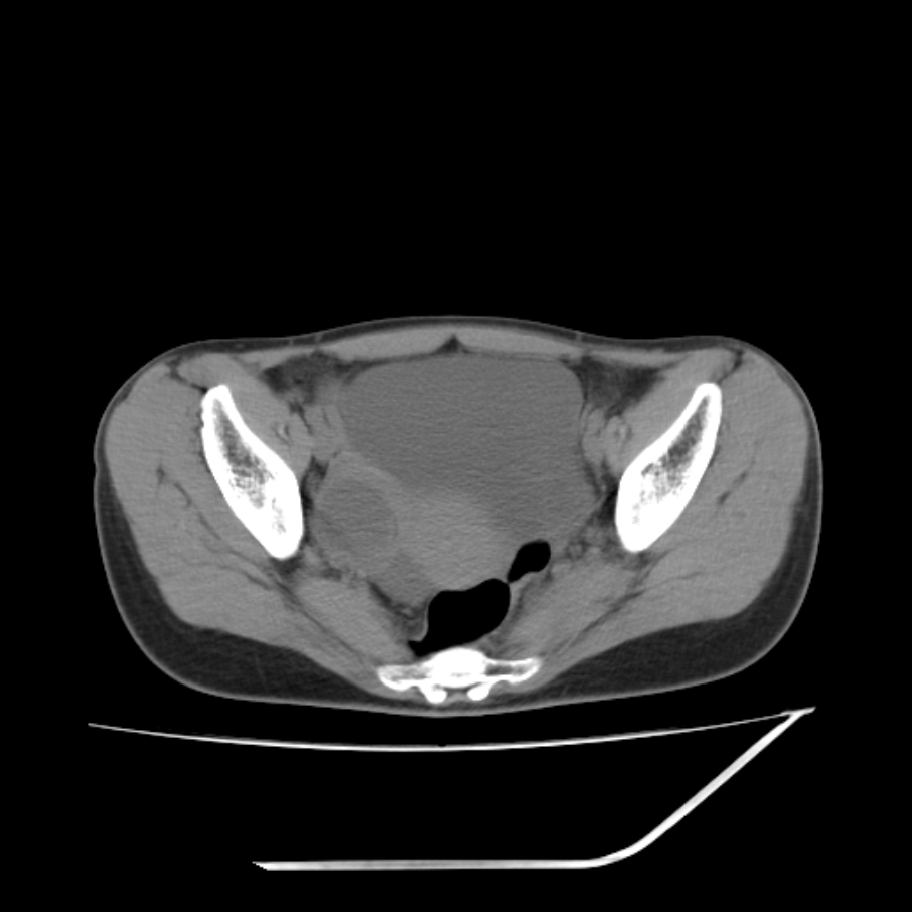

女,25岁。偶尔有右下腹不适感,余无明显异常。(结婚半年),囊壁较厚,是卵巢囊肿吗?

其上一层面见两枚小气泡影,考虑为肠管影可能,不完全除外囊肿

右侧卵巢区椭圆形囊性肿物,内壁光滑 无分隔。直肠子宫间隙内有少量积液征象。结合临床考虑卵巢巧克力囊肿,还要问问有没有痛经,本例ct怎么没有灌肠?要是灌肠或前一前口服造影剂,起码可以和肠管区别开

b超示:囊实性占位,畸胎瘤?临床有痛经。

考虑右侧卵巢囊性占位性病变(巧克力囊肿?),盆腔积液有不排除宫外孕可能,请结合临床和b超。

右侧卵巢囊伴盆腔少量积液。